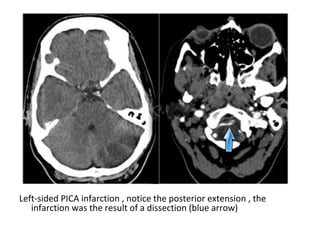

1-Posterior Inferior Cerebellar Artery (PICA in blue)

-The PICA territory is on the inferior occipital

surface of the cerebellum and is in equilibrium

with the territory of the AICA in purple which

is on the lateral side

-The larger the PICA territory , the smaller the

AICA and vice versa

Left-sided PICA infarction , notice the posterior extension , the

infarction was the result of a dissection (blue arrow)

Left sided PICA infarction, in unilateral infarcts there is always a sharp delineation in the midline

because the superior vermian branches do not cross the midline but have a sagittal course, this

sharp delineation may not be evident until the late phase of infarction, in the early phase, edema

may cross the midline and create diagnostic difficulties, infarctions at pontine level are usually

paramedian and sharply defined because the branches of the basilar artery have a sagittal

course and do not cross the midline, bilateral infarcts are rarely observed because these

patients do not survive long enough to be studied but sometimes small bilateral infarcts can

be seen